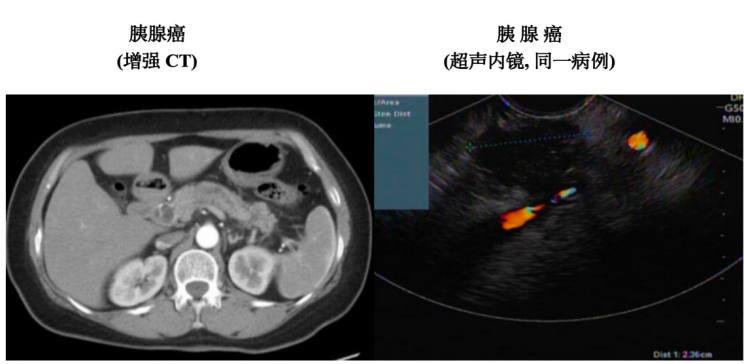

超声内镜结合内镜和超声技术,通过内镜将高频超声探头送入消化道,对胰腺进行近距离扫描。这种技术能突破传统超声受胃肠道气体、腹壁脂肪的干扰,清晰显示胰腺细微结构,甚至发现微小肿瘤,助力早期胰腺癌的检出。

在定性诊断上,超声内镜的“实时引导穿刺” 功能至关重要。医生可在实时监控下精准穿刺病变组织,获取样本进行病理检查,明确肿瘤性质,将诊断准确性提升至 90% 以上,为后续治疗指明方向。

同时,超声内镜能清晰显示肿瘤与周围组织的关系,判断肿瘤侵犯范围及淋巴结转移情况,为临床分期和治疗方案制定提供依据,有效避免漏诊或误诊。随着医学技术的发展,超声内镜在胰腺癌的早期诊断、精准分期和个体化治疗指导等方面,价值将持续凸显,为患者带来更多希望。